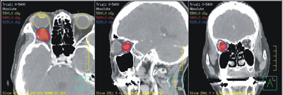

經確診與病情評估之後,黃醫師認為分段式放射治療為其首選治療,轉由放射腫瘤科的謝忱希醫師接手治療阿嬤的視神經鞘腦膜瘤。隨著放射治療技術的進步,從傳統二維、三維放射治療、強度調控放射治療,至今弧形強度調控放射治療與控影像導引放射治療(如:圖二),在在提升了治療的精準度,同時增加了治癒率與降低副作用。目前視神經鞘腦膜瘤接受放射線治療的五年控制率約為90-100%,而十年控制率為86-100%。過去令人詬病的副作用,例如:視神經傷害、視網膜傷害、三叉神經傷害、顏面神經傷害、認知功能傷害等,在治療計畫順型度增加,散射的放射劑量明顯縮小下,副作用明顯的降低了。

美國國家癌症訊網對第一級腦膜瘤也提出了45-54Gy的高度順型分次放療的建議。目前多數醫院主要使用的放射治療技術,為強度調控放射治療(Intensity-Modulated Radiation Therapy, 簡稱IMRT), 相較於過去傳統技術而言,可大幅減少治療相關毒性,達到更佳的醫療效益。

但最近這一、二年所推出的弧形強度調控放射治療 (Volumetric Modulated Arc Therapy, 簡稱 VMAT ) ,又再將其優勢更往前推進一步。弧形強度調控放射治療與螺旋刀則是可依照臨床需求,設計放射治療的照野及劑量,其放射治療射束則以弧形動態連續給予,在給予射束的同時並持續變化照射角度。因為射束的高變化性及多角度選擇性,讓放射治療選擇性變的更大且更具彈性,因此可達到較佳的設計治療品質。

此外在射束動態給予的過程中,即時在不同角度進行射束的強度調控達到最佳化,因此可讓高劑量儘量集中於腫瘤區域,而讓正常組織之傷害降低,提高治療效果及減輕副作用。另外可大幅縮短治療時間。同時藉由影像導引提昇治療精準度。

邱阿嬤接受弧形強度調控放射治療技術,每周連續五天治療54Gy,共計30次。治療後並未出現嚴重副作用。在接受27Gy後,顏色辨別力從1/15提高到13/15。經過54Gy治療後,右眼視力在9個月時從0.3增加到0.6,在15個月後提高到1.0。核磁共振顯示腫瘤密度輕度改變,腫瘤大小穩定。該治療為非侵入性,且在放射治療後15個月觀察到視力恢復正常。弧形強度調控放射治療技術可以有效治療視神經鞘腦膜瘤,降低副作用,然而仍需要更長時間的追蹤以評估長期影響與療效。

圖二、邱媽媽經過高階弧形強度調控治療技術54格雷治療,無任何嚴重併發症